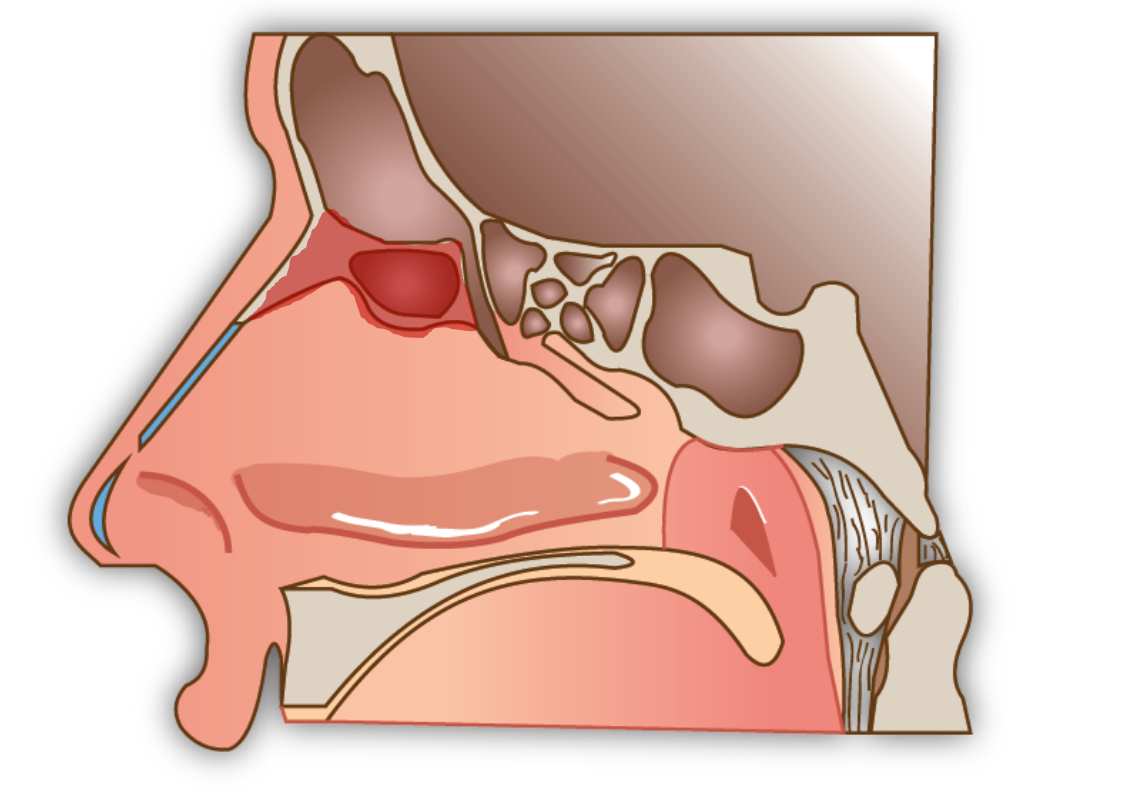

L’ouverture simple du sinus frontal (Sinusotomie Draf I)

Elle consiste en l’ouverture endoscopique, par les narines, des cellules de l’ethmoïde antérieure qui se situent en dessous du sinus frontal pour avoir accès à celui ci.

La sinusotomie frontale Draf II

Elle utilise la même technique endoscopique mais l’ouverture du sinus frontale est élargie dans sa partie basse à l’aide de fraises pour permettre un meilleur drainage

La sinusotomie frontale Draf III

Il s’agit de l’intervention la plus technique par voie endonasale. Elle consiste à fraiser le plancher des deux sinus frontaux et à les réunir en fraisant la cloison qui les sépare. Elle nécessite un temps de cicatrisation important après la chirurgie et des lavages de fosse nasales réguliers.